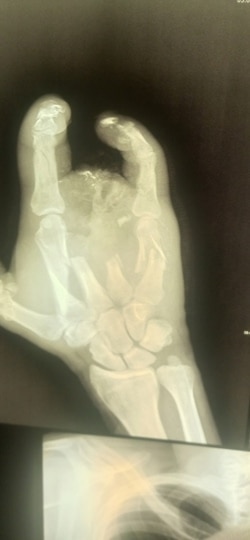

– Как меня вытащили, как везли до полевого госпиталя – не помню ни черта. Очнулся, узнал, что получил осколочное ранение, обжег шею, глаз, невзрывное осколочное ранение оторвало мне полруки, снесло все пальцы, разгромило всю кисть. Увезли меня в Луганск, там позволили три недели полежать, и все. Выпнули из военного госпиталя в обычную больницу. Я еще удивился, зачем на последние пять дней. Потом узнал.

Рука Алексея после ранения на войне

Оказалось, что с незажившими ранами покалеченного солдата отправили в гражданское медучредждение для того, чтобы на руках у него не было документов из военного госпиталя. И сейчас Алексей не может доказать, что стал калекой в бою.

– Прописали мази и перевязки. Я засомневался, что лечение нормальное, благо, был знакомый хирург. Я пришел к нему и очень вовремя – началось загноение на обрубке руки. Там он уже сделал все заново – чистка, вставил спицы и даже часть кости восстановить смог. Конечно, все за деньги. Всю "зарплату", что получил за войну, считай, все на хирурга и ушло! В итоге вышел "в минус", – подытоживает Алексей.

Протез Алексей пытается получить с начала 2023 года.